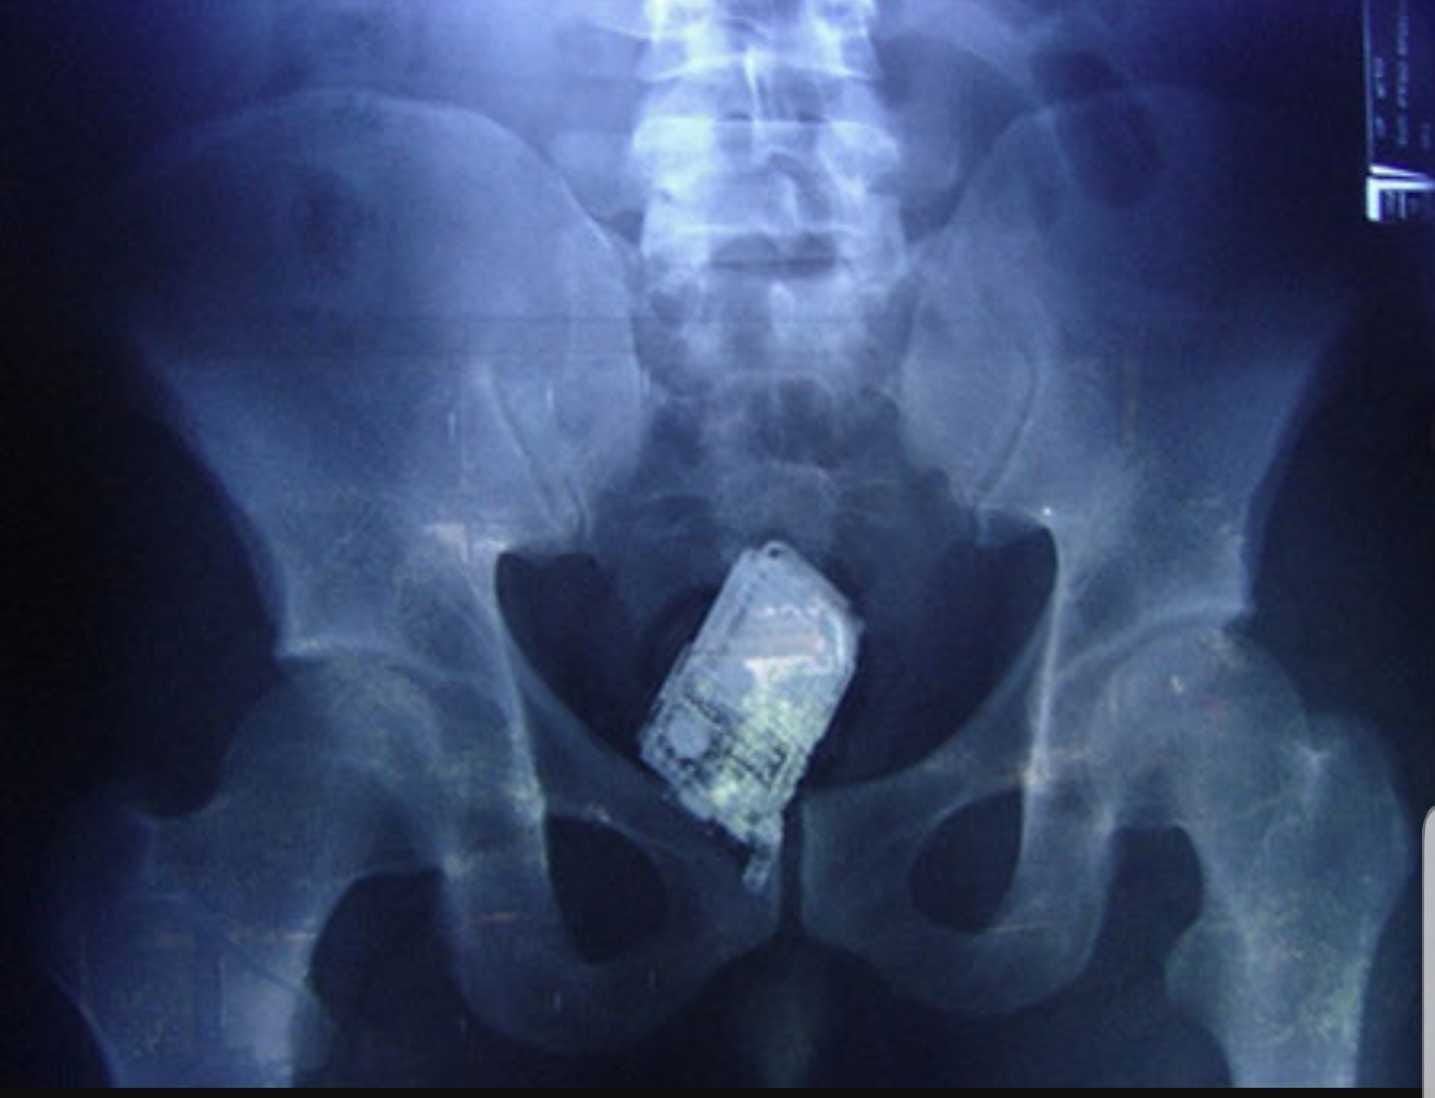

Teléfono móvil dentro del cuerpo de un recluso. / Cadena SER

ACAIP afirma que los funcionarios deben hacer frente a esta realidad con medios claramente insuficientes ya que los terminales, cada vez más pequeños y fabricados con componentes plásticos, escapan fácilmente a los detectores de metales y pueden esconderse en los lugares más insospechados. Esto obliga a realizar requisas exhaustivas que requieren formación especializada y suficiente personal, algo que hoy en día no se garantiza en todos los centros.